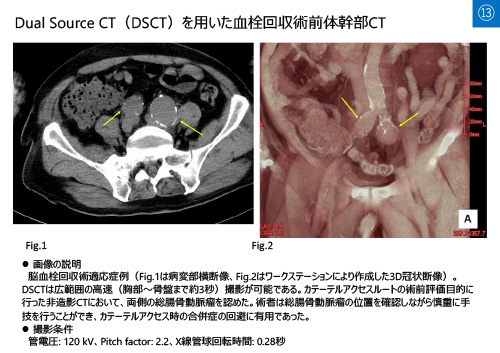

No.13 サムネイル

No.13

「血栓回収術前体幹部CTが有用であった症例」

佐藤 祐一郎

(秋田県立循環器・脳脊髄センター 放射線部)